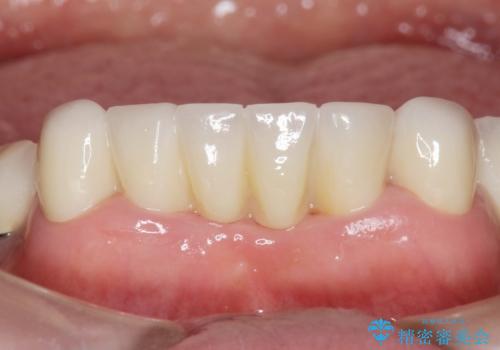

抜歯後歯肉の治癒を十分に待ったのち、ブリッジによる補綴治療を行いました。

- ¥1,010,000 (仮歯×9本、ファイバーコア×1本、ジルコニアクラウン スタンダード×9本)費用は治療当時の料金となります

自然な仕上がりと使い心地に喜んで頂けました。

ジルコニアクラウン スタンダード